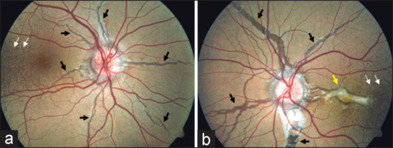

Bilateral angioid streaks in a young patient with pseudoxanthoma elasticum.

一名年轻假黄瘤患者的双侧血管样条纹。